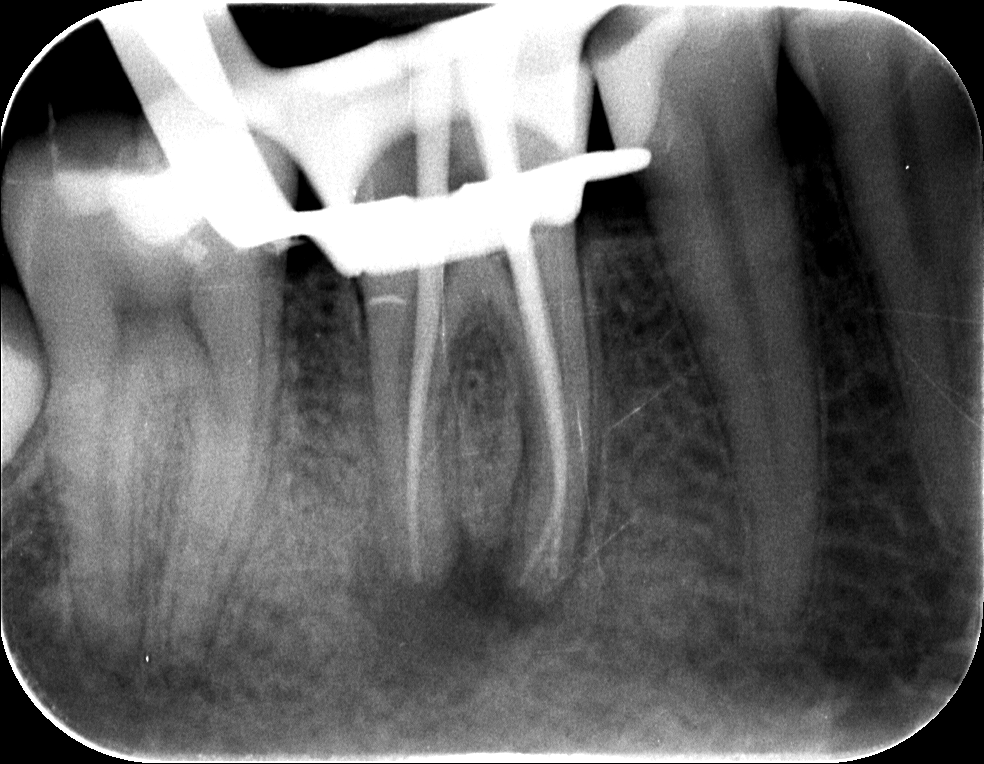

Dr. Kovács Kitti páciense egy három éve készült gyökértöméssel kapcsolatos panaszával kereste fel rendelőnket. A kérdéses fog az utóbbi időben bizonytalan panaszokat produkált. Néha kifejezetten fájt, néha a páciens „érezte”, hogy van foga, néha pedig teljesen panaszmentes volt. A vizsgálatot egy kis röntgenfelvétel készítésével kezdtük, majd ezt tüzetes szájüregi vizsgálat követte. A fog kopogtatásra érzékeny volt, illetve a röntgenfelvételen egyértelműen látható a csontban lévő krónikus gyulladás (amelyet az alsó képen pirossal rajzoltunk körbe), illetve az ezt kiváltó ok, a rövid gyökértömés (amelynek hiányzó szakaszát sárgával jelöltük).

mikroszkópos gyökérkezelés 1.kép